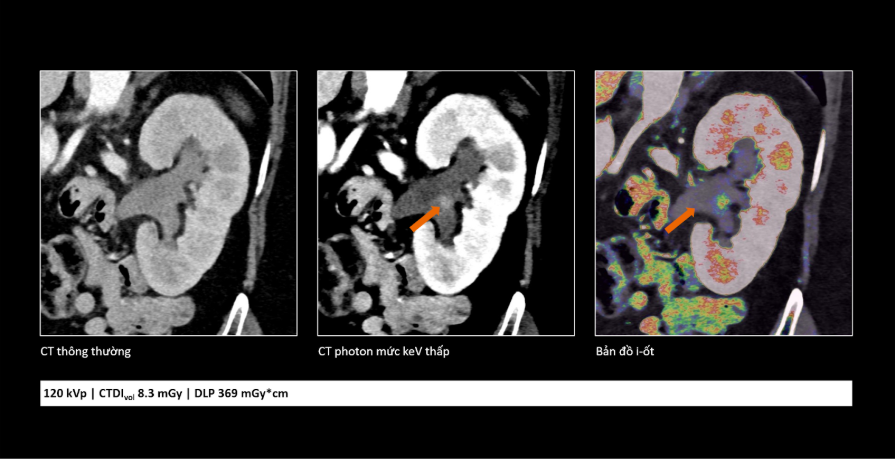

Trong ung thư, việc phát hiện sớm những tổn thương rất nhỏ đóng vai trò quan trọng trong hiệu quả điều trị. Công nghệ cắt lớp vi tính lượng tử cho phép tái tạo hình ảnh với lát cắt rất mỏng (tới 0,2 mm), giúp phát hiện những bất thường mà trước đây có thể bị bỏ sót. Nhờ đó, bác sĩ có thể nhận diện sớm các dấu hiệu bất thường và đánh giá chính xác hơn đặc tính tổn thương, hỗ trợ hiệu quả trong chẩn đoán sớm cũng như theo dõi tái phát.

So sánh cho thấy công nghệ cắt lớp vi tính lượng tử không chỉ giúp hình ảnh rõ hơn mà còn cung cấp thêm thông tin, hỗ trợ bác sĩ đánh giá tổn thương chính xác hơn.

Bên cạnh khả năng cải thiện chất lượng hình ảnh, công nghệ cắt lớp vi tính lượng tử còn giúp giảm đáng kể liều tia X và lượng thuốc cản quang sử dụng. Điều này góp phần tăng mức độ an toàn cho người bệnh, đặc biệt với những người có nguy cơ suy thận hoặc mắc bệnh lý nền phức tạp.